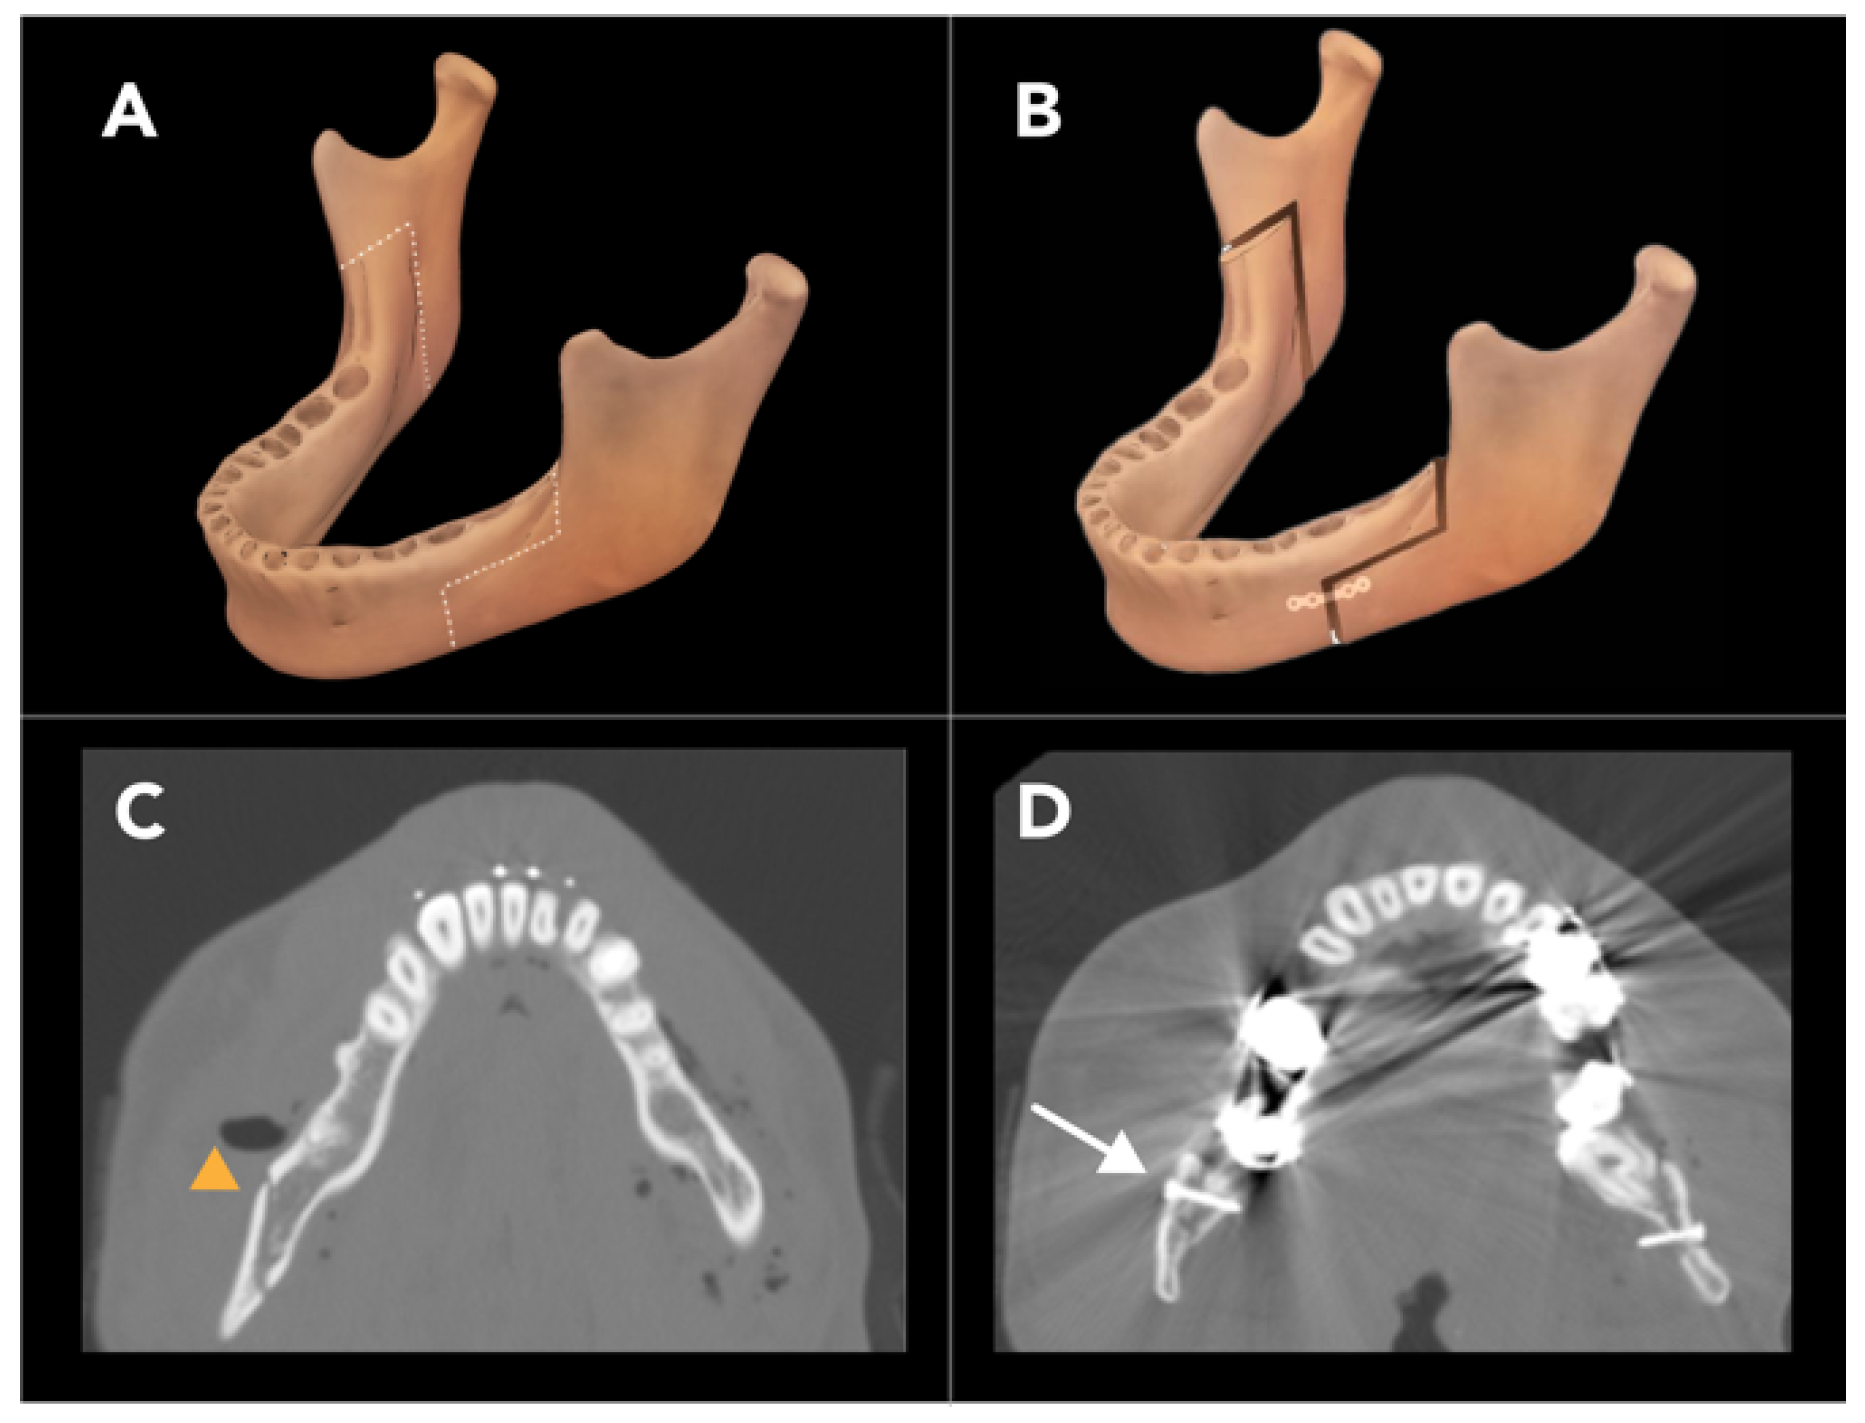

2.1.4. Bilateral Sagittal Split Osteotomy